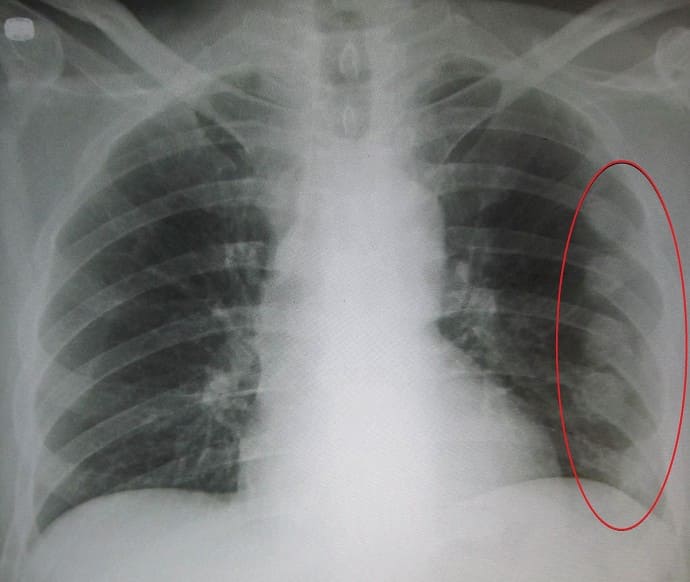

- Пневмоторакс. Повреждение тканей легкого приводит к накоплению воздуха в плевральной полости и сдавлению органов грудной клетки. При отсутствии своевременной медицинской помощи пневмоторакс может становиться напряженным и вызывать остановку сердца и смерть пострадавшего. Для предотвращения его развития закрытый пневмоторакс необходимо сделать открытым (в передней стенке грудной клетки выполняется пункция, создающая отверстие для выхода воздуха наружу).

- Гемоторакс. Разрыв сосудов отломками ребер приводит к скоплению крови в плевральной полости. У больного появляется одышка и дыхание затрудняется. При массивном кровотечении и отсутствии медицинской помощи, заключающейся в его остановке и удалении скопившейся крови при помощи пункции, наступает дыхательная недостаточность.

- при пневмотораксе – выполняется пункция плевральной полости для выведения воздуха и восстановления нормального давления в легких при помощи вакуумного насоса;

- при обширном гемотораксе – выполняется пункция плевральной полости для выведения крови (при небольшом объеме крови пункция не проводится и кровь рассасывается самостоятельно).